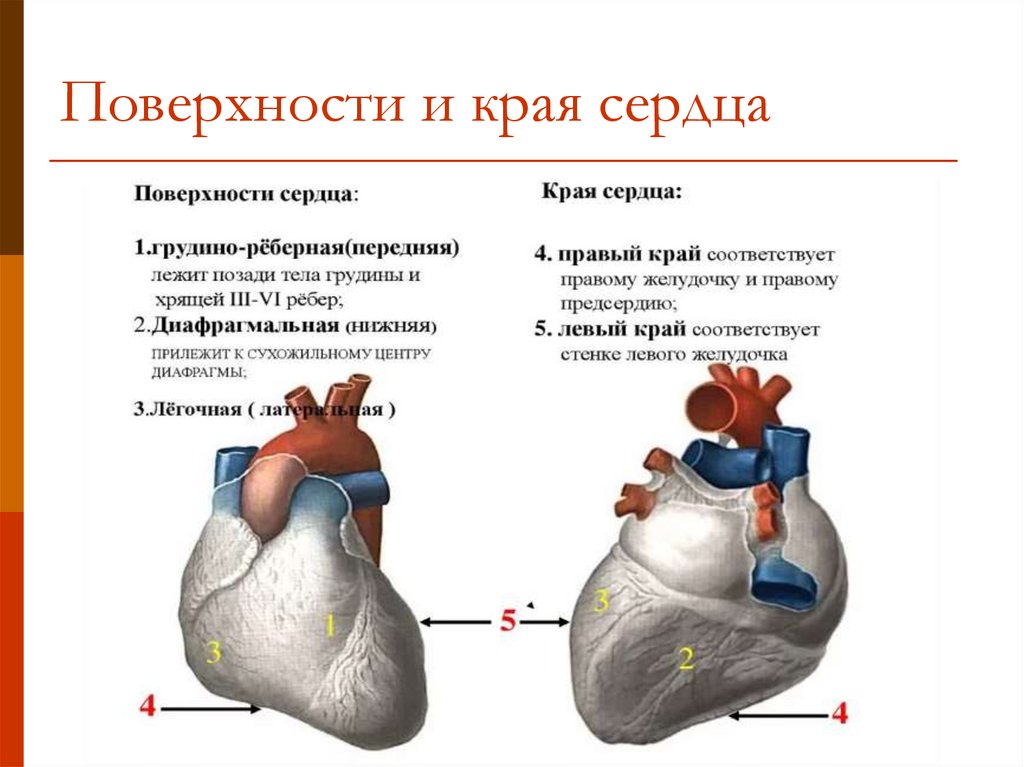

Анатомия Сердца: Расположение и Функции